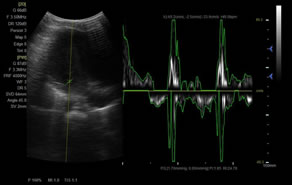

> 脈沖頻譜多普勒成像(PW)